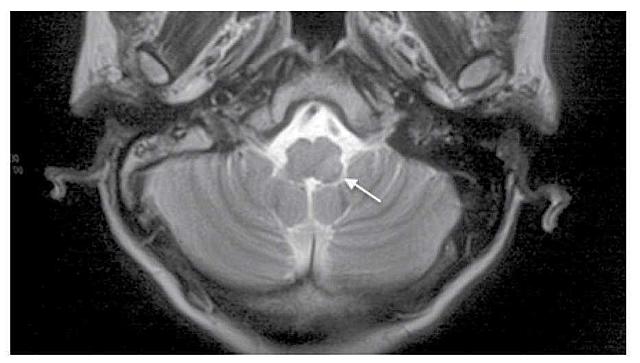

En el electrocardiograma realizado se advierten datos de fibrilación auricular. Ademas se realiza RM (imagen)